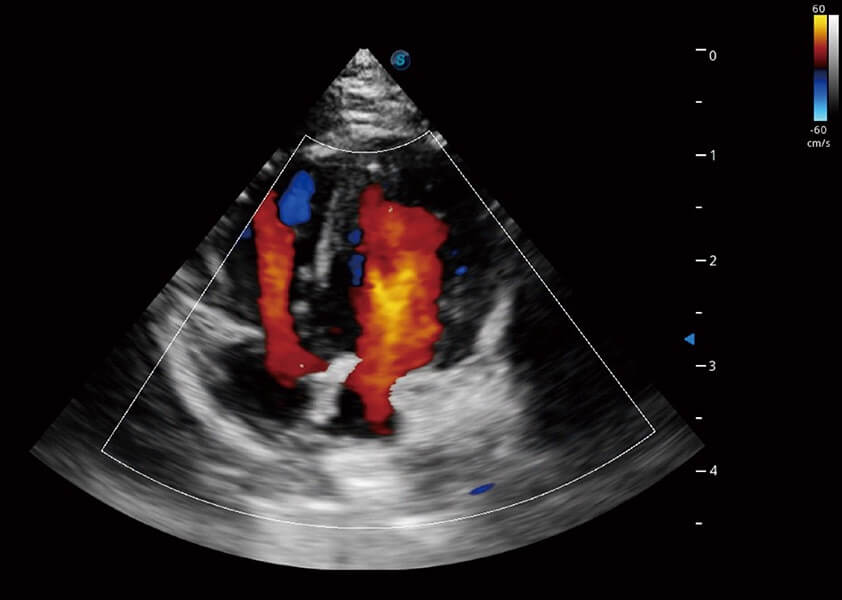

ProPet 60 作为一款高端台式动物超声设备,为动物医生的日常诊断提供了一系列贴合动物临床需求、解决临床实际问题的高级成像功能。凭借全系列高清探头,满足医生对腹部、心脏、生殖、浅表、肌骨等成像的所有需求,切实帮助您提升检查效率,提高诊断信心。

动物是人类最亲密的朋友和最值得信赖的伙伴。环球UG官网也一直致力于探索动物专用的超声影像解决方案。 全新推出的ProPet系列,是环球UG官网在动物超声影像智能化、专业化、精准化的一次跨越式革新。动物不能用言语来表述自己的不适,通过超声影像,ProPet系列搭建了动物医生与不同物种沟通的“桥梁”,为动物医生注入了“治愈之力”。